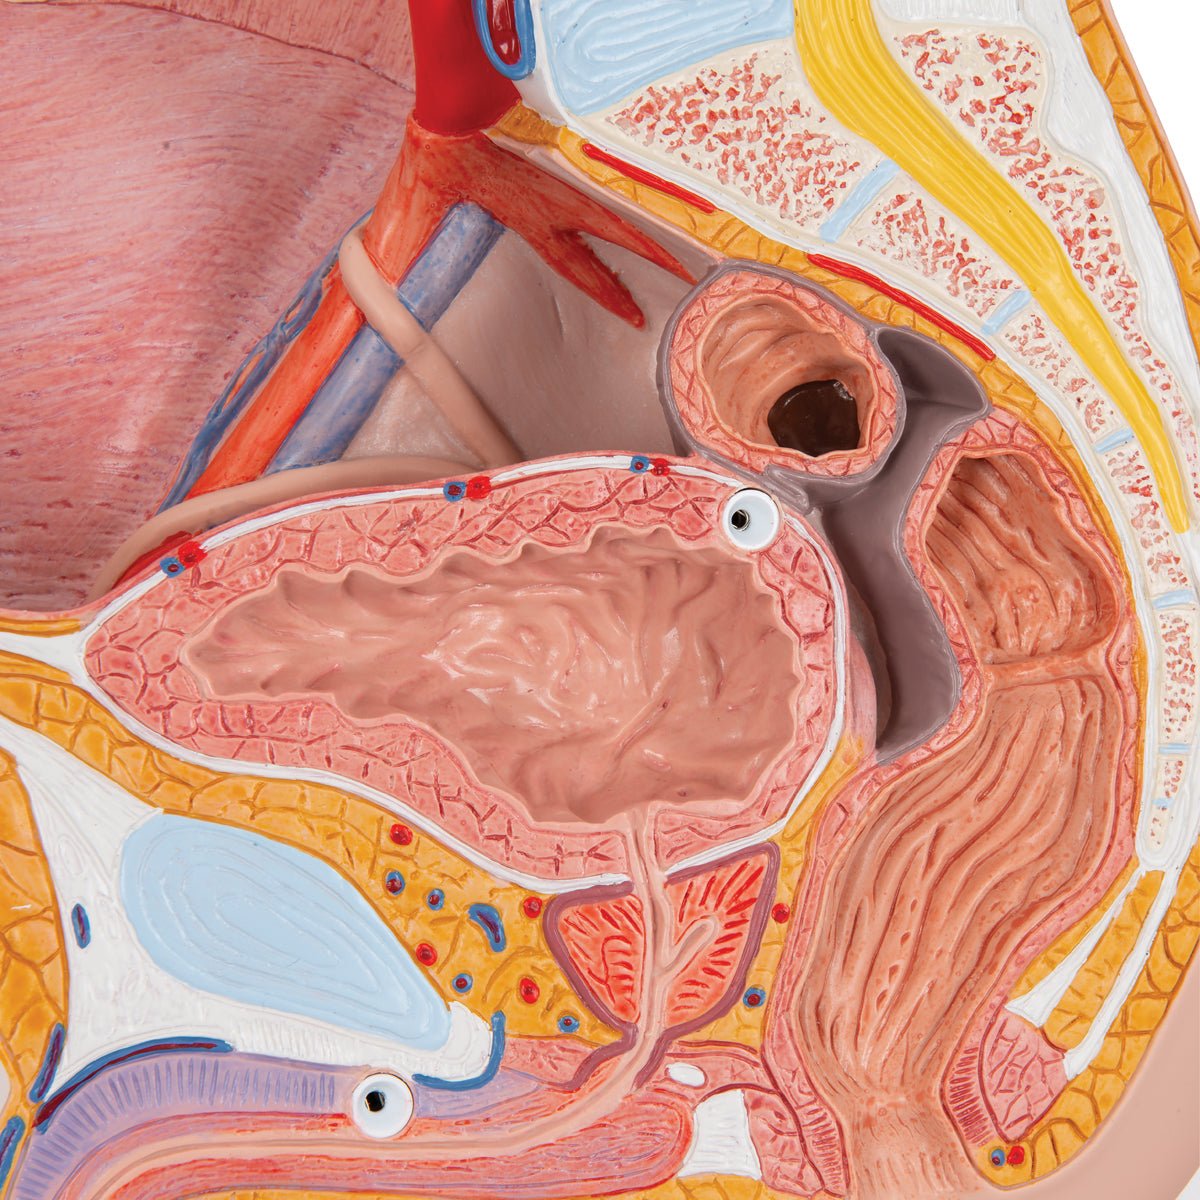

Salg af anatomiske modeller er det bærende element i eAnatomi, selvom vi også bruger mange ressourcer på at udvikle vores egne anatomiske materialer som fx plakater. Anatomiske modeller anvendes til forskellige formål og kan både vise afgrænset væv, organer samt organsystemer. Søger du en simpel model af knoglevæv eller måske en avanceret torso-model baseret på MRI teknologi, kan du finde det hele på eanatomi.com.